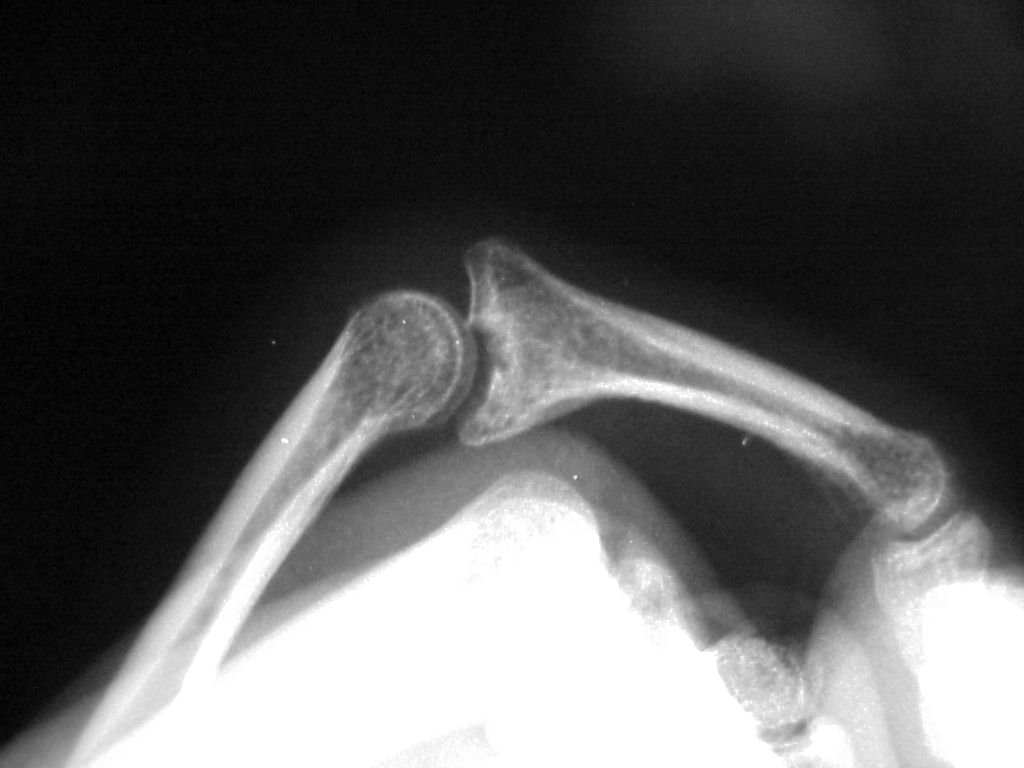

Shotgun view of the pathology: the dorsal half of the base of the middle phalanx appears preserved, the palmar half recessed and covered with scar: